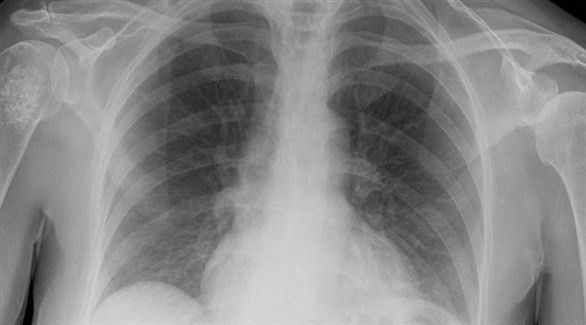

الحساسية والربو في أعقاب عاصفة رملية من المشاكل الموسمية، وإلى جانب هذه المشكلة هناك التهاب الرئتين الذي ينتج عن التعرض المكثّف للرياح المحمّلة بالغبار.

تقوم الشعيرات الموجودة في القصبة الهوائية بتنقية الهواء من الرمال، لكن نتيجة العواصف يدخل إلى الجهاز التنفسي كمية كبيرة من هذه الرمال تثير الحساسية أو يحمل بعضها جراثيم تنقل العدوى. إليك أهم الأعراض وطرق تنظيف الرئتين:

السعال المتكرّر، والصفير أثناء الشهيق أو الزفير مع ألم الصدر من أهم الأعراض المشتركة للحساسية والتهاب الرئتين بعد استنشاق غبار عاصفة رملية. وقد يؤدي السعال المتكرّر مع صعوبة التنفس إلى خدوش في الرئة.